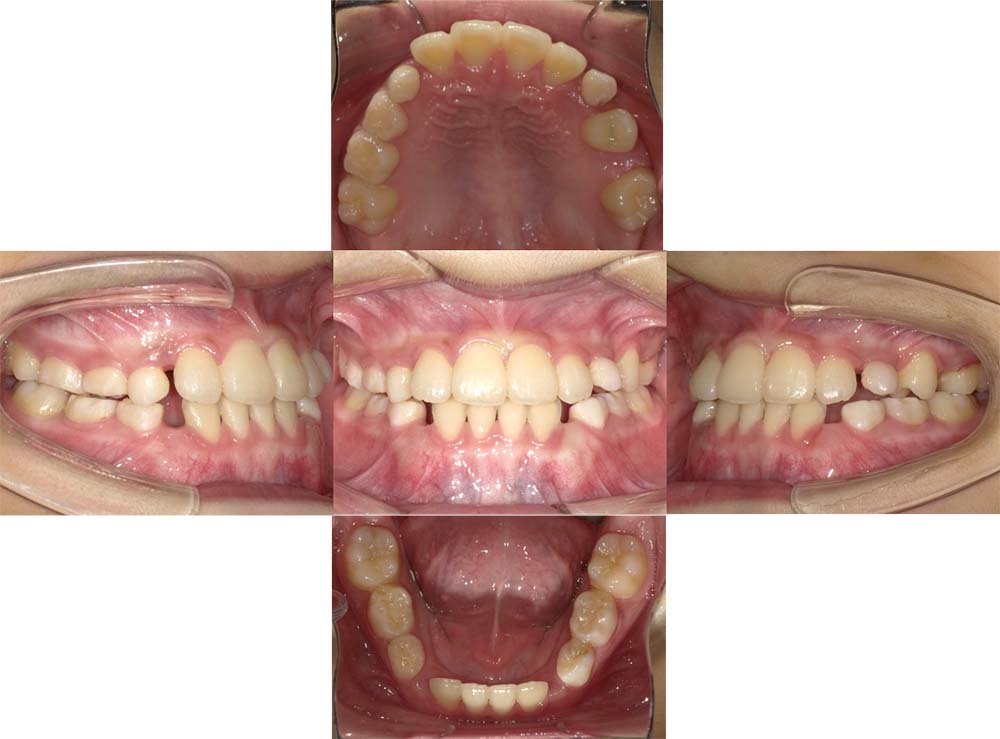

症例01

| 主訴 | 歯並びがガタガタしている。 |

| 診断名あるいは主な症状 | 叢生 |

| 年齢/性別 | 22歳・男性 |

| 矯正ステージ | 大人の矯正治療 |

| 治療方法 | ワイヤー矯正 |

| 抜歯部位/抜歯有無 | 非抜歯 |

| 治療内容 | 上顎大臼歯の遠心移動により前歯のガタガタを排列スペースを獲得し全顎的な排列を行った。 |

| 費用 | 85万円程度(2025.10時点の料金となります。) ※矯正基本料金、審美ブラケットを含む |

| 治療期間 | 2年4ヶ月 |

| 主なリスク・副作用 | 痛み、歯根吸収、歯肉退縮、虫歯、後戻り |